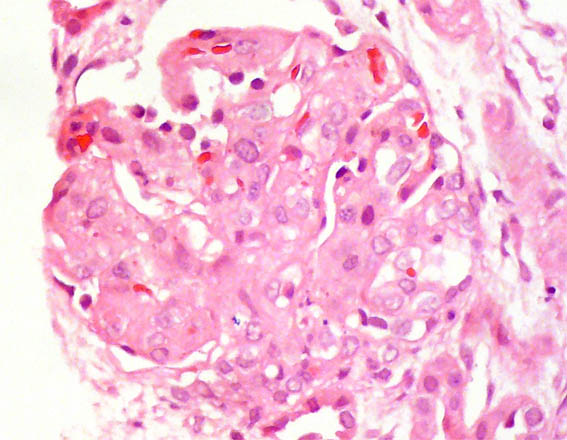

Se hace biopsia renal. Observe las imágenes.

Figura 1. H&E, X100.